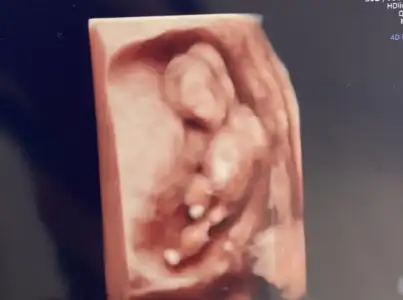

12+2 de ultrasonda bakmıştı doktor bey.. bence de çok erken cinsiyet tahmini için.. ulstrasonda da bu şekilde görüldü bebeğim. bilemiyorum artık hayırlısı🥹

Eklentiler

• IMG_8115.webp

IMG_8115.webp

12,7 KB · Görüntüleme: 99

Bacak arasında bir şey görünüyor ama 12. Haftada o kadar büyük olur mu bilemedim 🤭

Ufak bir kabariklik mi mevcut erkek gibi geldi bana sağlıkla alın inşallah